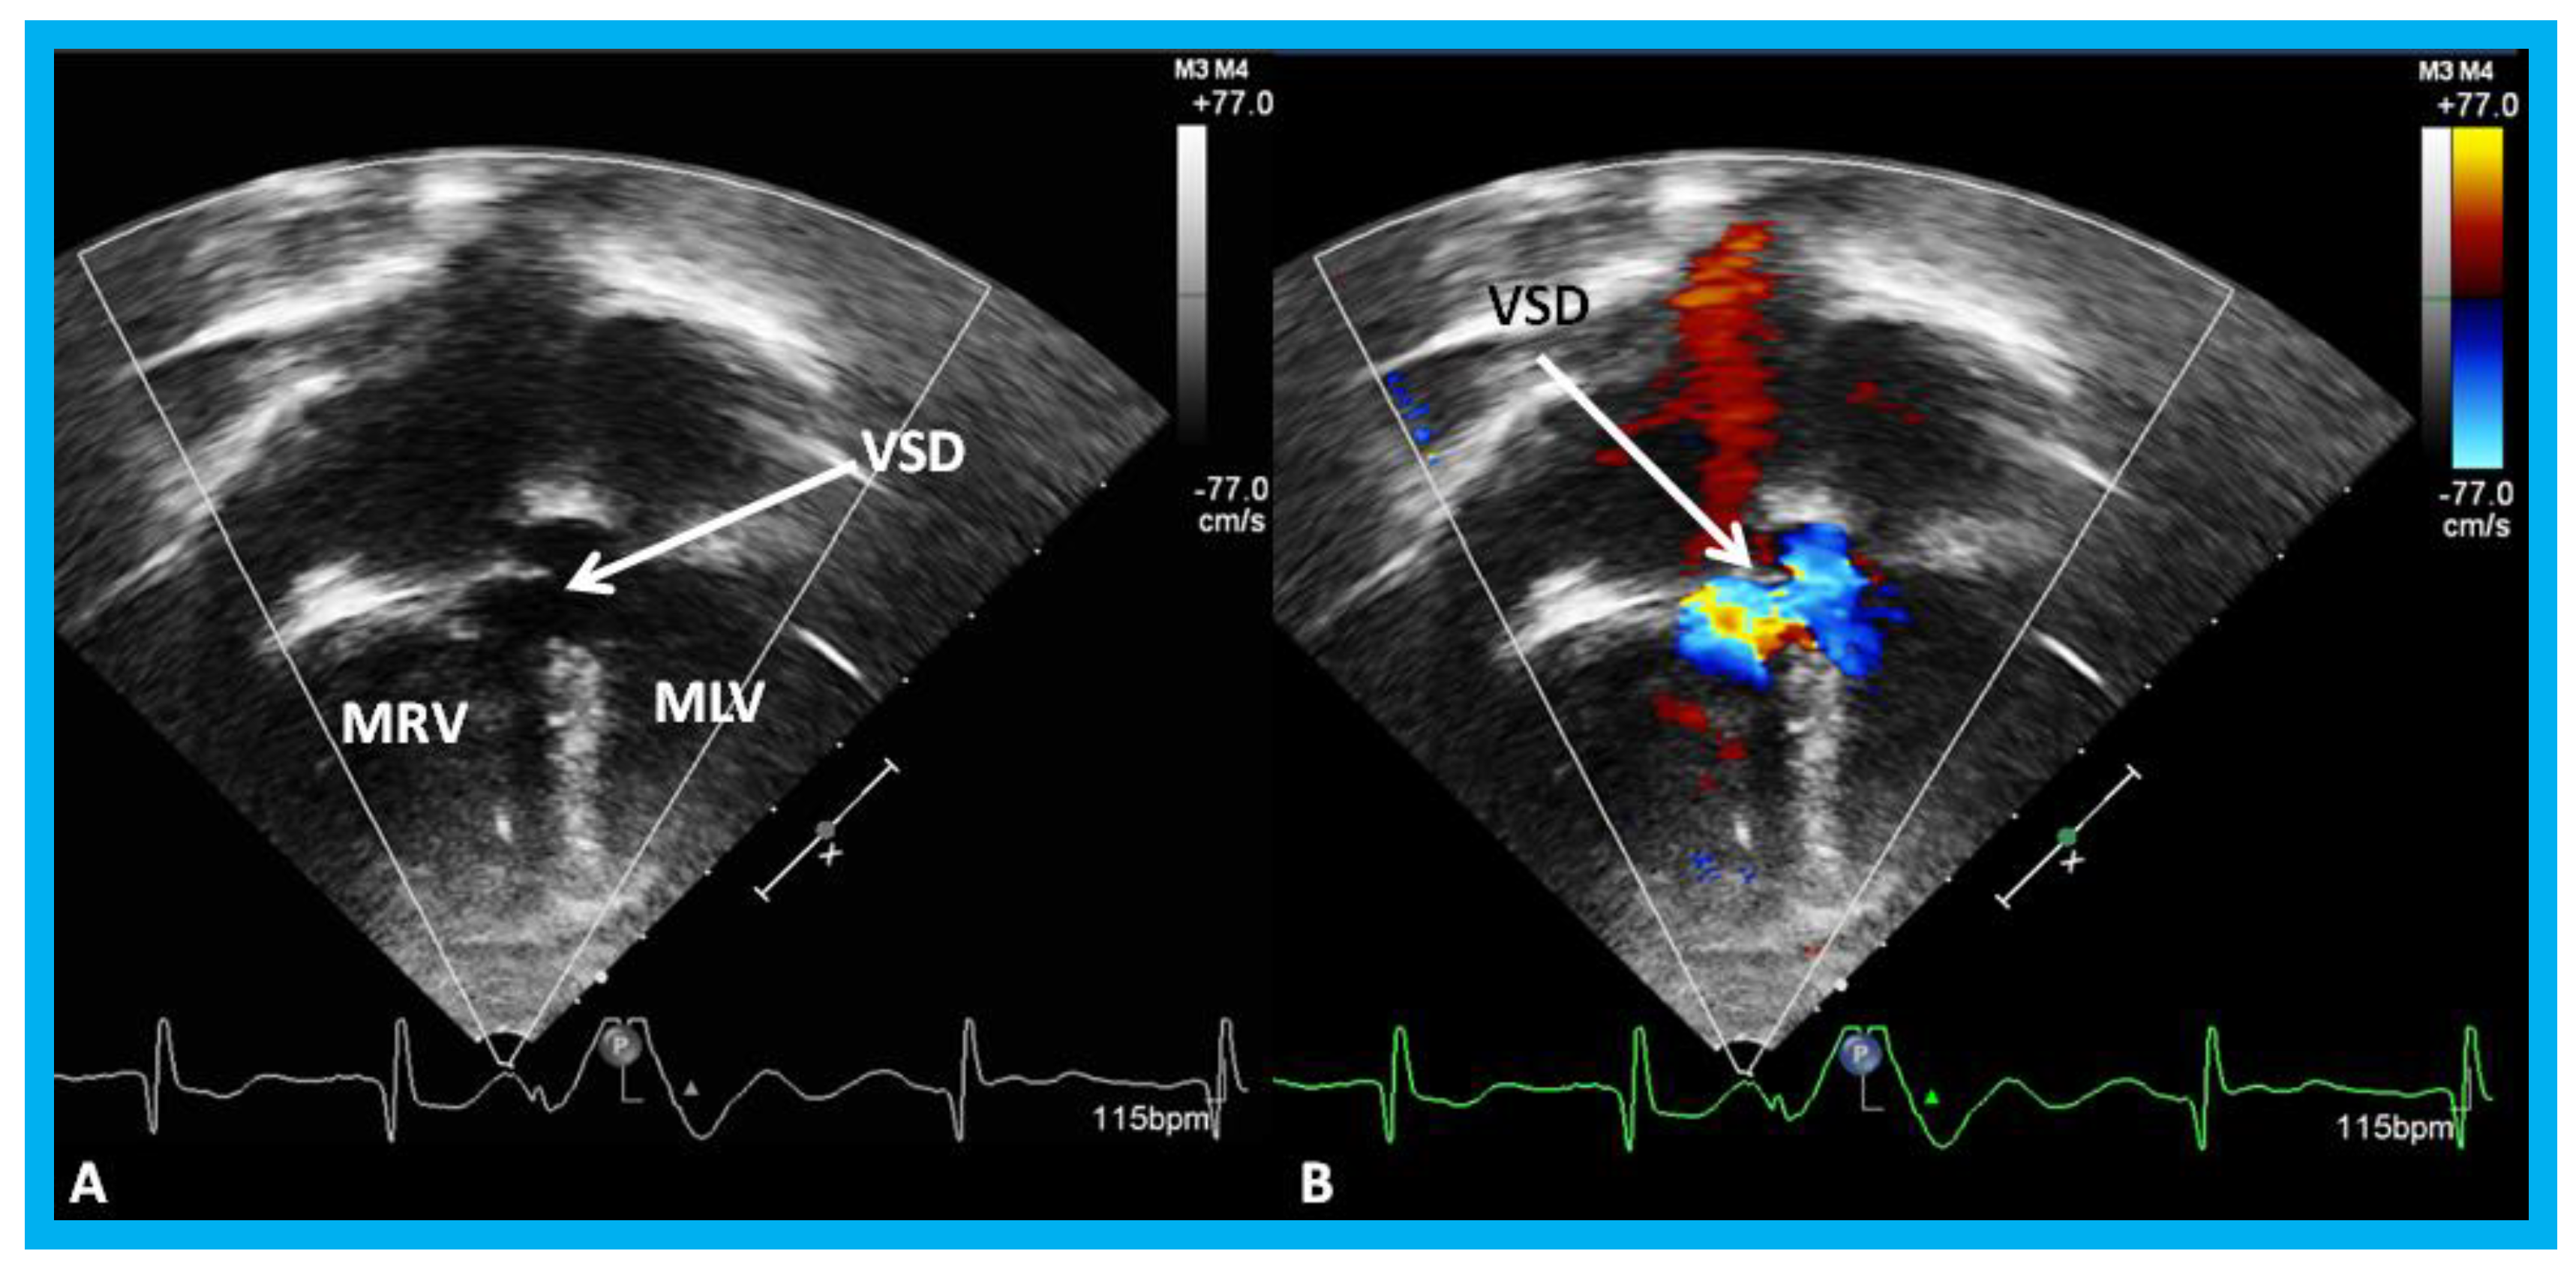

Figure 18. Selected video frames by two-dimensional (A) and with color flow imaging (B) from apical four-chamber view from the right chest demonstrating morphologic right (MRV) and morphologic left (MLV) ventricles and a large VSD (ventricular septal defect) in a patient with dextrocardia. Reproduced from Yarrabolu T.R., et al. [23].